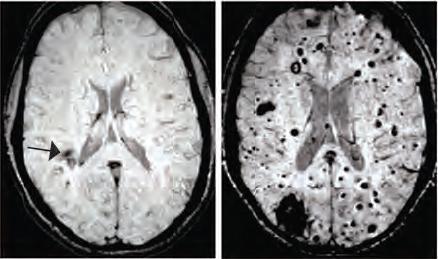

Cerebral cavernous malformations (CCMs) are clusters of dilated, thin-walled blood vessels that can lead to seizures or stroke when blood leaks into the surrounding brain tissue. A team of scientists at the University of Pennsylvania investigated the mechanisms that cause CCM lesions to form in genetically engineered mice and discovered an unexpected link to bacteria in the gut. When bacteria were eliminated the number of lesions was greatly diminished.

The question remained as to how bacteria in the blood could influence blood vessel behavior in the brain. Gram-negative bacteria produce molecules called lipopolysaccharides (LPS) that are potent activators of innate immune signaling. When the mice received injections of LPS alone, they formed numerous large CCMs, similar to those produced by bacterial infection. Conversely, when the LPS receptor, TLR4, was genetically removed from these mice they no longer formed CCM lesions. The researchers also found that, in humans, genetic mutations causing an increase in TLR4 expression were associated with a greater risk of forming CCMs.